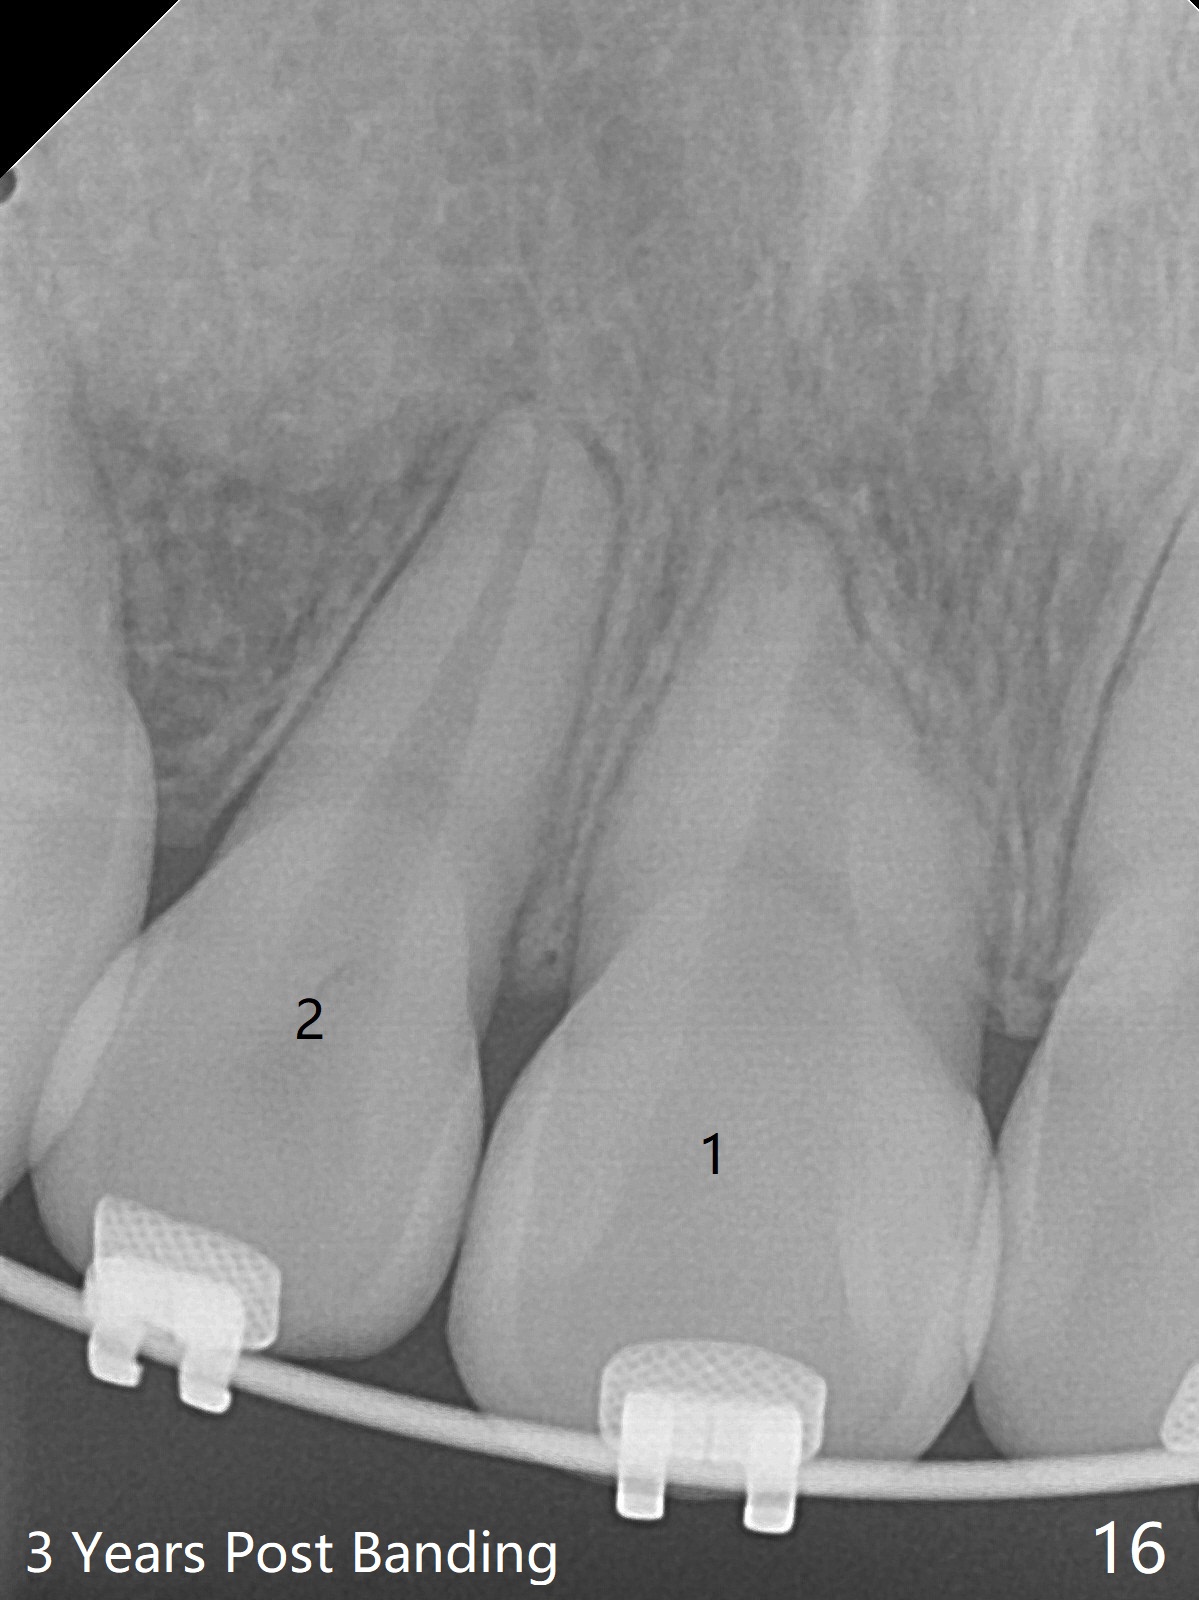

Thirteen months post banding, U dental midline apparently coincides with facial one, diastemata: UL2/3, UL6/7, L3-3, UL post detached, placed crimpable mini post mesial to UL2, closed spring UL2-7. Three-4 weeks later, diastema appears between UL1/2, while that of UL6/7 closes. Continue closed spring between UL2/7, while adding power chains U2-2 (Fig.12). To correct anterior overjet (Fig.13), Class II retraction is introduced bilaterally (Fig.14). After mesialization of LL3 (with Class I canine occlusion), L3-3 are being ligated as an anchor to mesialize LL5 (Fig.15). Occlusion appears to be Class II nearly 3 years post banding. Miniimplants are planned to distalize the upper dentition. Upper anterior PAs are taken to determine whether the roots of the upper anterior teeth have been resorbed. In fact, they are (Fig.16,17). Fortunately the anterior overjet does not look so severe. Orthodontic treatment should be terminated soon. Next case PAs should be taken prior to distalization.